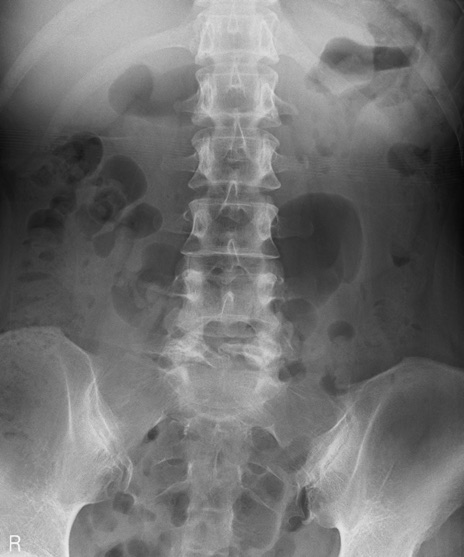

【整形】TIPS症例4 腰椎レントゲン(正面像)

【症例】30歳代男性

【主訴】腰痛、両大腿後面の痛み

【現病歴】高校時代に●●を指摘されたが経過観察されてきた。体動時の腰痛があり、長時間立位、坐位にて両大腿後面の痛みを感じる。外来にて経過観察されてきたが改善ない。

【身体所見】SLR 60/60、TA5/5,EHL 5/5,FHL 5/5、psoas 5/5、quad 5/5、PTR+/+、ATR+/+、babinski-/-、長時間歩行で症状あるがなんとか歩いている。安静時痛なし。体動時、長時間立位、坐位にて症状あり。

異常所見と診断は?